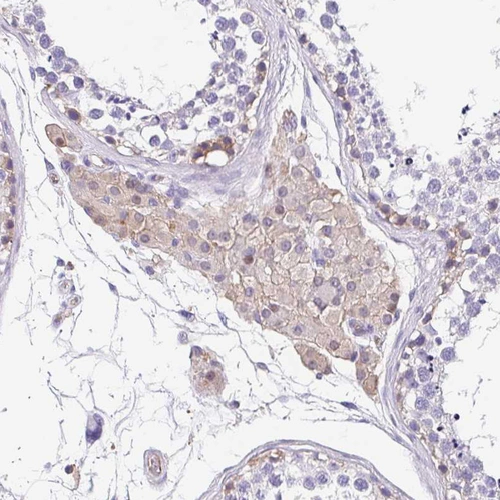

Immunohistochemical staining of human lung shows moderate cytoplasmic positivity in pneumocytes.